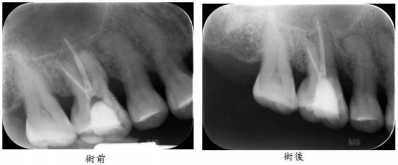

5.52歲男性患者自述右上第一大臼齒頰側牙齦反覆腫脹已經持續1個月,臨床檢查發現患齒頰側牙齦有明顯的腫 脹(swelling)並有輕微的觸痛感,此外在附連牙齦(attached gingiva)有竇管(sinus tract)出現,同時患 齒咬合面有明顯磨耗現象,於近心頰側牙根的頰側與舌側均有深且窄(8~10 mm)的牙周囊袋,並有敲痛與 咬痛的問題,放射線學檢查結果如下圖所示。則患齒的問題最有可能是下列何者所引起?

(A)慢性根尖周圍炎(chronic apical periodontitis) (B)牙根穿孔(root perforation) (C)垂直牙根斷裂(vertical root fracture) (D)側邊牙周囊腫(lateral periodontal cyst)